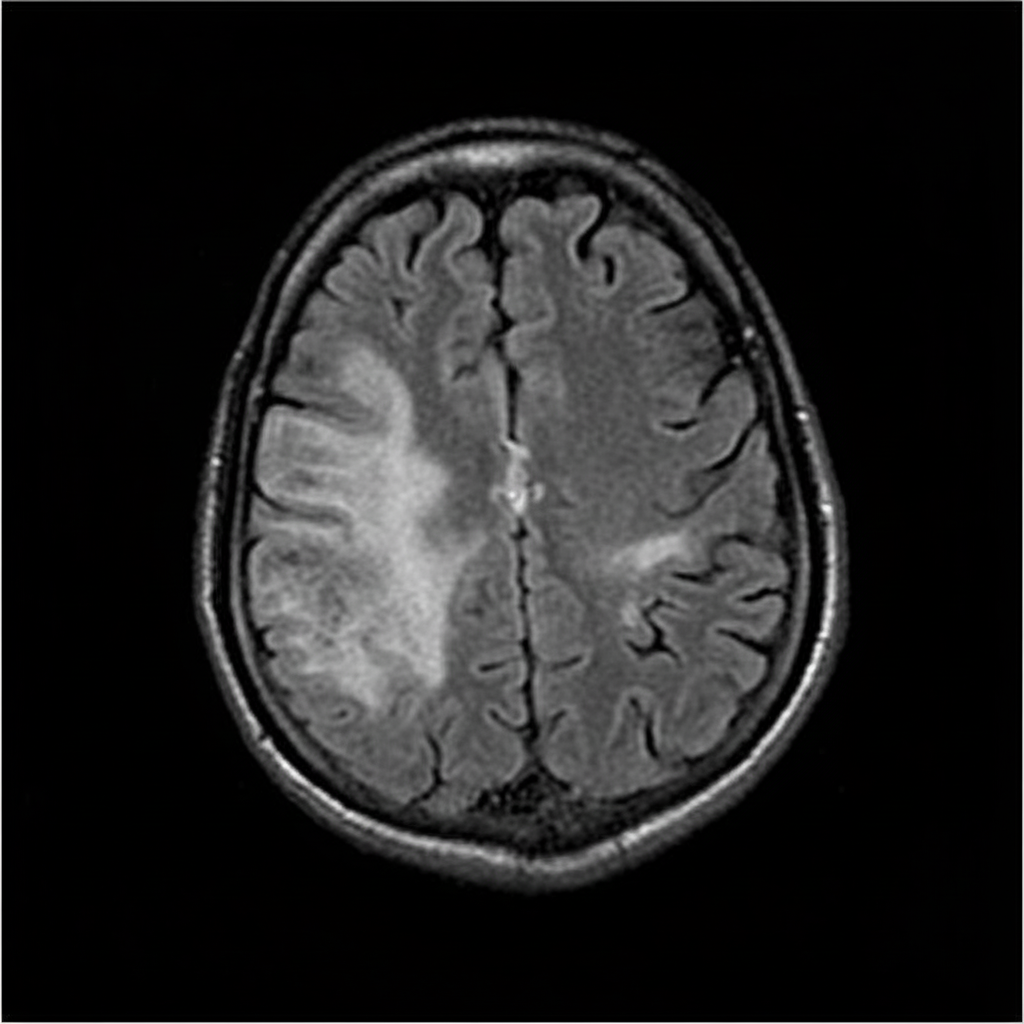

The MRI finding shown in the image is characteristic of which of the following pathologies?

Explanation: ***Multiple Sclerosis*** - **Periventricular white matter lesions** (Dawson's fingers) on **FLAIR MRI** are pathognomonic for multiple sclerosis, showing demyelinating plaques perpendicular to ventricles. - The **finger-like projections** extending from ventricles represent perivenular inflammation and demyelination characteristic of MS pathophysiology. *Sturge-Weber syndrome* - Typically shows **tram-track calcifications** in the cortex on CT imaging, not periventricular white matter lesions. - Associated with **leptomeningeal angiomatosis** and cortical atrophy, distinctly different from the shown MRI pattern. *Neurofibromatosis* - MRI findings include **schwannomas**, **optic gliomas**, and **café-au-lait spots**, not periventricular white matter lesions. - **Neurofibromas** along nerve pathways and **sphenoid wing dysplasia** are characteristic imaging features, absent in this case. *Tuberous Sclerosis* - Characteristic findings include **cortical tubers**, **subependymal nodules**, and **candle-guttering calcifications** on imaging. - **Subependymal giant cell astrocytomas** near the foramen of Monro are typical, not the periventricular pattern shown.